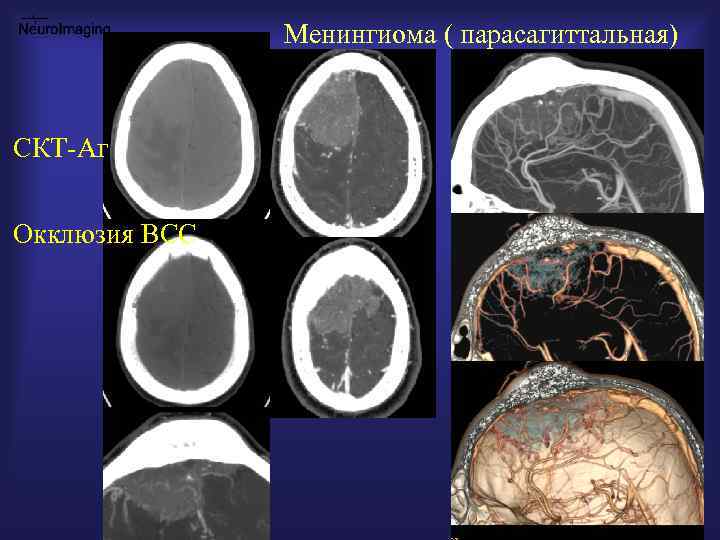

Менингиома ( парасагиттальная) СКТ-Аг Окклюзия ВСС

Менингиома ( МРТ/ СКТ - перфузия, ангиография) От анатомии К физиологии